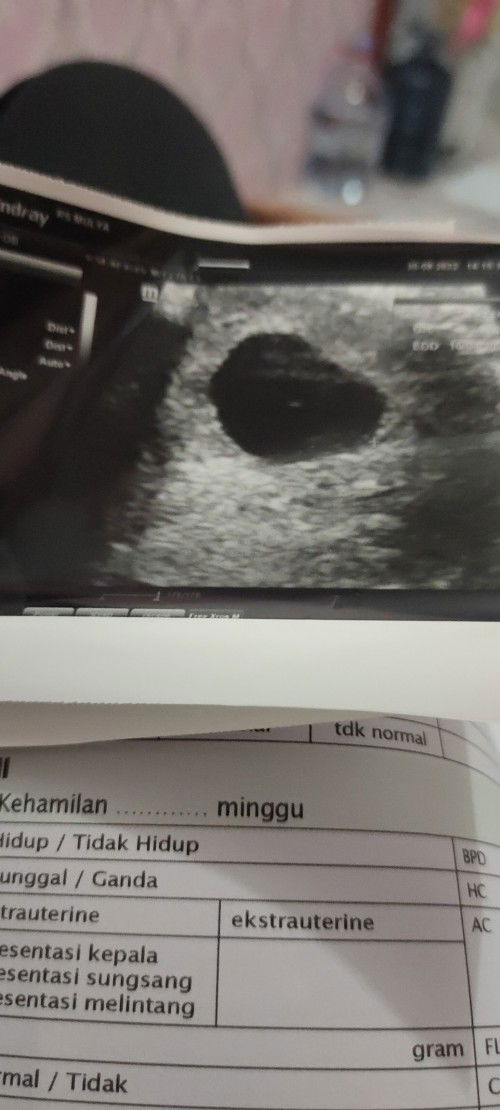

Kehamilan BO

Menurut bunda gimana? Padahal saya gak keluar flek, barusan abis usg di rumah sakit. Pas denger dokter ngmng bgtu, air mata langsung netes gatau harus gimana padahal anak pertama yg ditunggu2 .

HAMIL BO 7minggu

Bund disini ada yg pernah ngalamin kehamilan kosong? Saya abis usg baru ada kantong rahimnya blm ada janin, dokter minta segera di kuret, menurut bunda gimana? Saya masih pertahanin dan berpikir positif